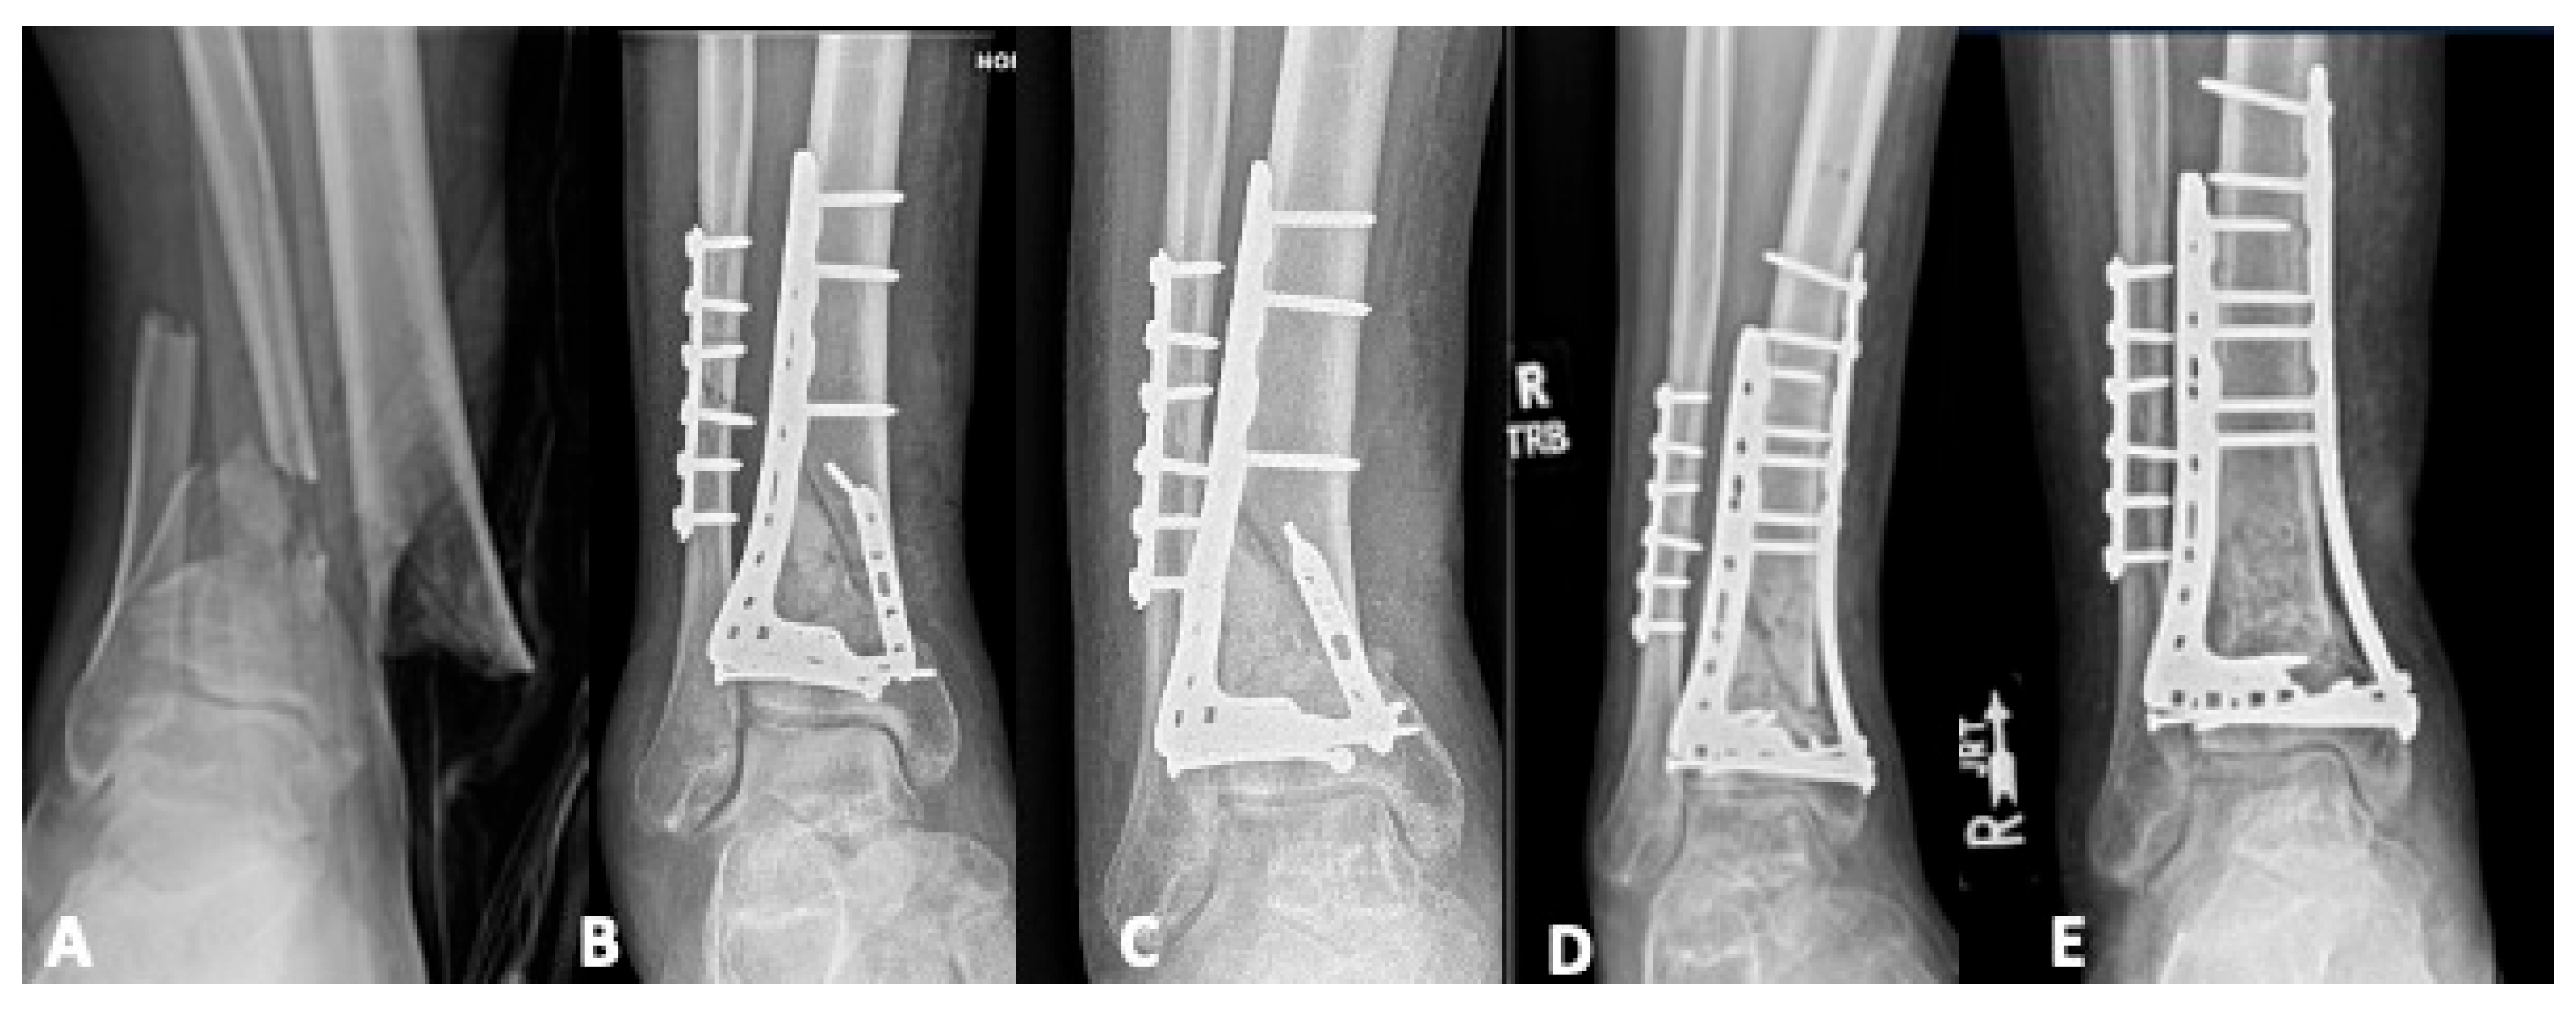

5.1. Revision Operative Fixation

5.2.2. Tibiotalar Arthrodesis